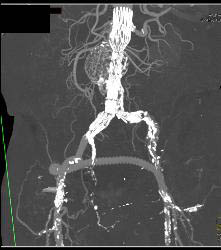

CTA Runoff With Occluded Left Popliteal Artery